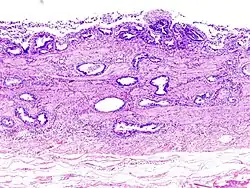

Histopatologia de um adenocarcinoma da vesícula